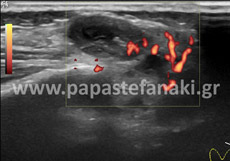

Υπερηχογράφημα Οσχέου

Στο υπερηχογράφημα οσχέου ελέγχεται η θέση, το μέγεθος και η μορφολογία των όρχεων και των επιδιδυμίδων καθώς και η αιμάτωση των αγγείων της περιοχής.

- Οσχέου

• Οσχέου